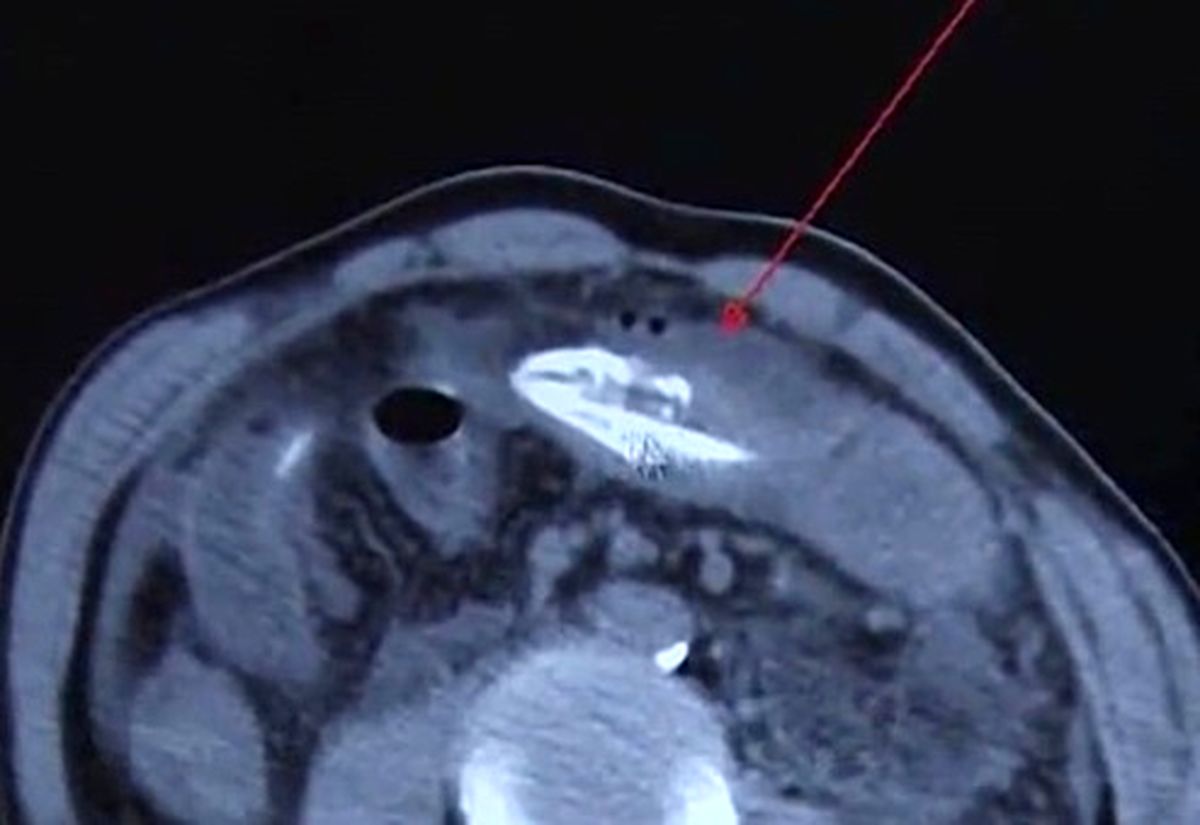

باشگاه خبرنگاران: یک مرد میانسال چینی که از شکم درد شدید خود کلافه شده بود پس از مراجعه به بیمارستان با صحنه‌ای عجیب روبه رو شد. پزشکان پس از انجام آزمایش CT یک مارماهی مرده ۱۶ اینچی را که در معده این مرد گیر کرده بود پیدا کردند.

این مرد پس از شکم درد شدید خود به بیمارستان «هوانگ جیانگ» در دونگ گوان واقع در استان گوانگ دونگ چین مراجعه کرده بود. پزشکان جراح پس از یک عمل جراحی موفق به خارج کردن این جانور از معده این بیمار ۵۰ ساله شدند. دکتر لی، یکی از پزشکان تیم جراحی گفت: «ما مشکوک به وجود یک جسم خارجی در معده این بیمار بودیم. پس از انجام آزمایش سی تی اسکن یک جانور را در معده این بیمار مشاهده کردیم. حین فرآیند لاپروسکوپی متوجه شدیم این جانور یک مار ماهی است. ظاهرا این مرد طبق یک روش درمان سنتی برای پاکسازی اقدام به قورت دادن این مارماهی کرده بود.»